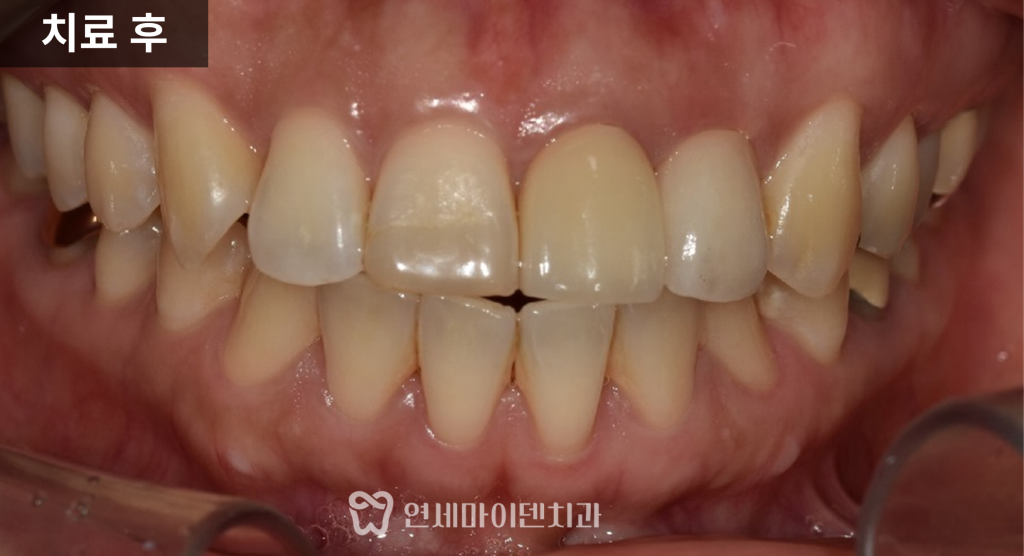

앞니 크라운, 자연스럽게 만드는 기준

앞니 치료에서는 기능만큼 중요한 것이

자연스러운 심미성입니다.

모든 치아를 동일하게 하얗게 만드는 것이 아니라,

기존 자연치아의 색조와 조화를 맞추는 것이 핵심입니다.

이 케이스에서도

기존 크라운은 중간 톤이 어색하게 노랗게 보여

자연스럽지 않은 상태였고,

반대편 자연치아의 색을 기준으로

톤을 맞추어 보철을 제작

했습니다.